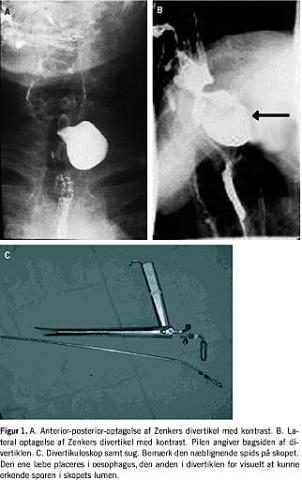

Behandlingen er kirurgisk og tidligere altid gennem åben lateral adgang på halsen, men nu oftest som endoskopisk behandling med enten laser eller stapleteknik. Den endoskopiske teknik er første gang beskrevet af Dohlmann et al [4]. Dohlmann anvendte en elektroslynge, men siden har flere nyere teknikker, heriblandt CO2 -laser, overtaget. Præoperativt sikres diagnosen ved, at der foretages røntgenundersøgelse af oesophagus. Man fremstiller både forfra og sideoptagelse efter indgift af barium kontast peroralt [3] (Figur 1A og B ). Størrelsen af divertiklet er af mindre betydning ved beslutningen om operation, hvis de ovennævnte symptomer er til stede, dog kan det være teknisk vanskeligt at behandle meget små divertikler endoskopisk, idet placeringen af divertikuloskopet vanskeliggøres af de små pladsforhold.

Proceduren indledes med rigid øsofagoskopi i generel anæstesi for at bedømme divertiklets størrelse og placering samt forholdene i oesophagus distalt for divertiklet. Herefter placeres divertikuloskopet (Figur 1 C) som vist i Figur 2 . Herefter placeres en våd svamp i oesophagus og sporen mellem oesophagus og divertikel brændes ned med CO2 -laser. Efterfølgende placeres det rigide øsofagoskop igen for at sikre fri passage.